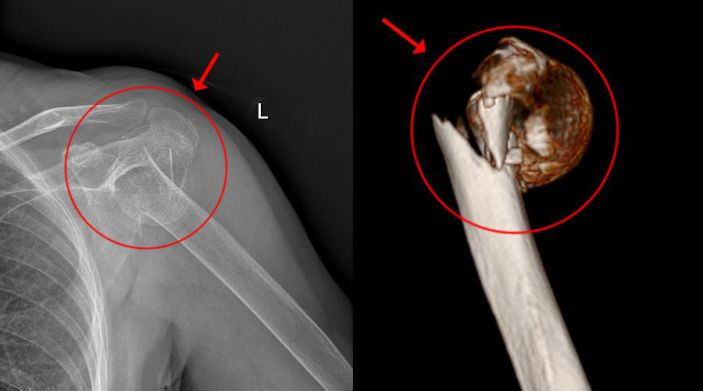

經CT檢查發現,患者的左肱骨上段粉碎性骨折,骨盆左恥骨上下肢骨折。此外,老太太還伴有老年性骨質疏松、雙側頸動脈明顯粥樣硬化、高血壓病、高脂血症等疾病。

骨科主任吳志斌考慮到患者骨盆左恥骨骨折未有明顯移位,可行保守治療,而左肱骨上段粉碎性骨折,需待患者病情穩定、可耐受手術後,行肩關節置換術。患者家屬表示願意配合一切治療。

吳主任根據CT+三維重建先行拟訂詳細的手術方案。9月4日在經過充分的術前準備後,老太太被送進了層流淨化手術室,行左側人工肱骨頭置換術。家屬在手術室外焦急地等待,而此時手術室内的吳志斌主任在麻醉科的配合下,根據方案有條不紊地開展手術,娴熟地取出左肱骨頭,并給予安裝肱骨假體,考慮到患者骨質疏松明顯,吳主任還特地加用了骨水泥。術中老太太未出現血壓下降及意識改變等其他不适,整個手術非常順利,再次給患者家屬滿意的答卷。經過醫護人員的對症治療、精心護理,老太太将于近日康複出院。

△術前